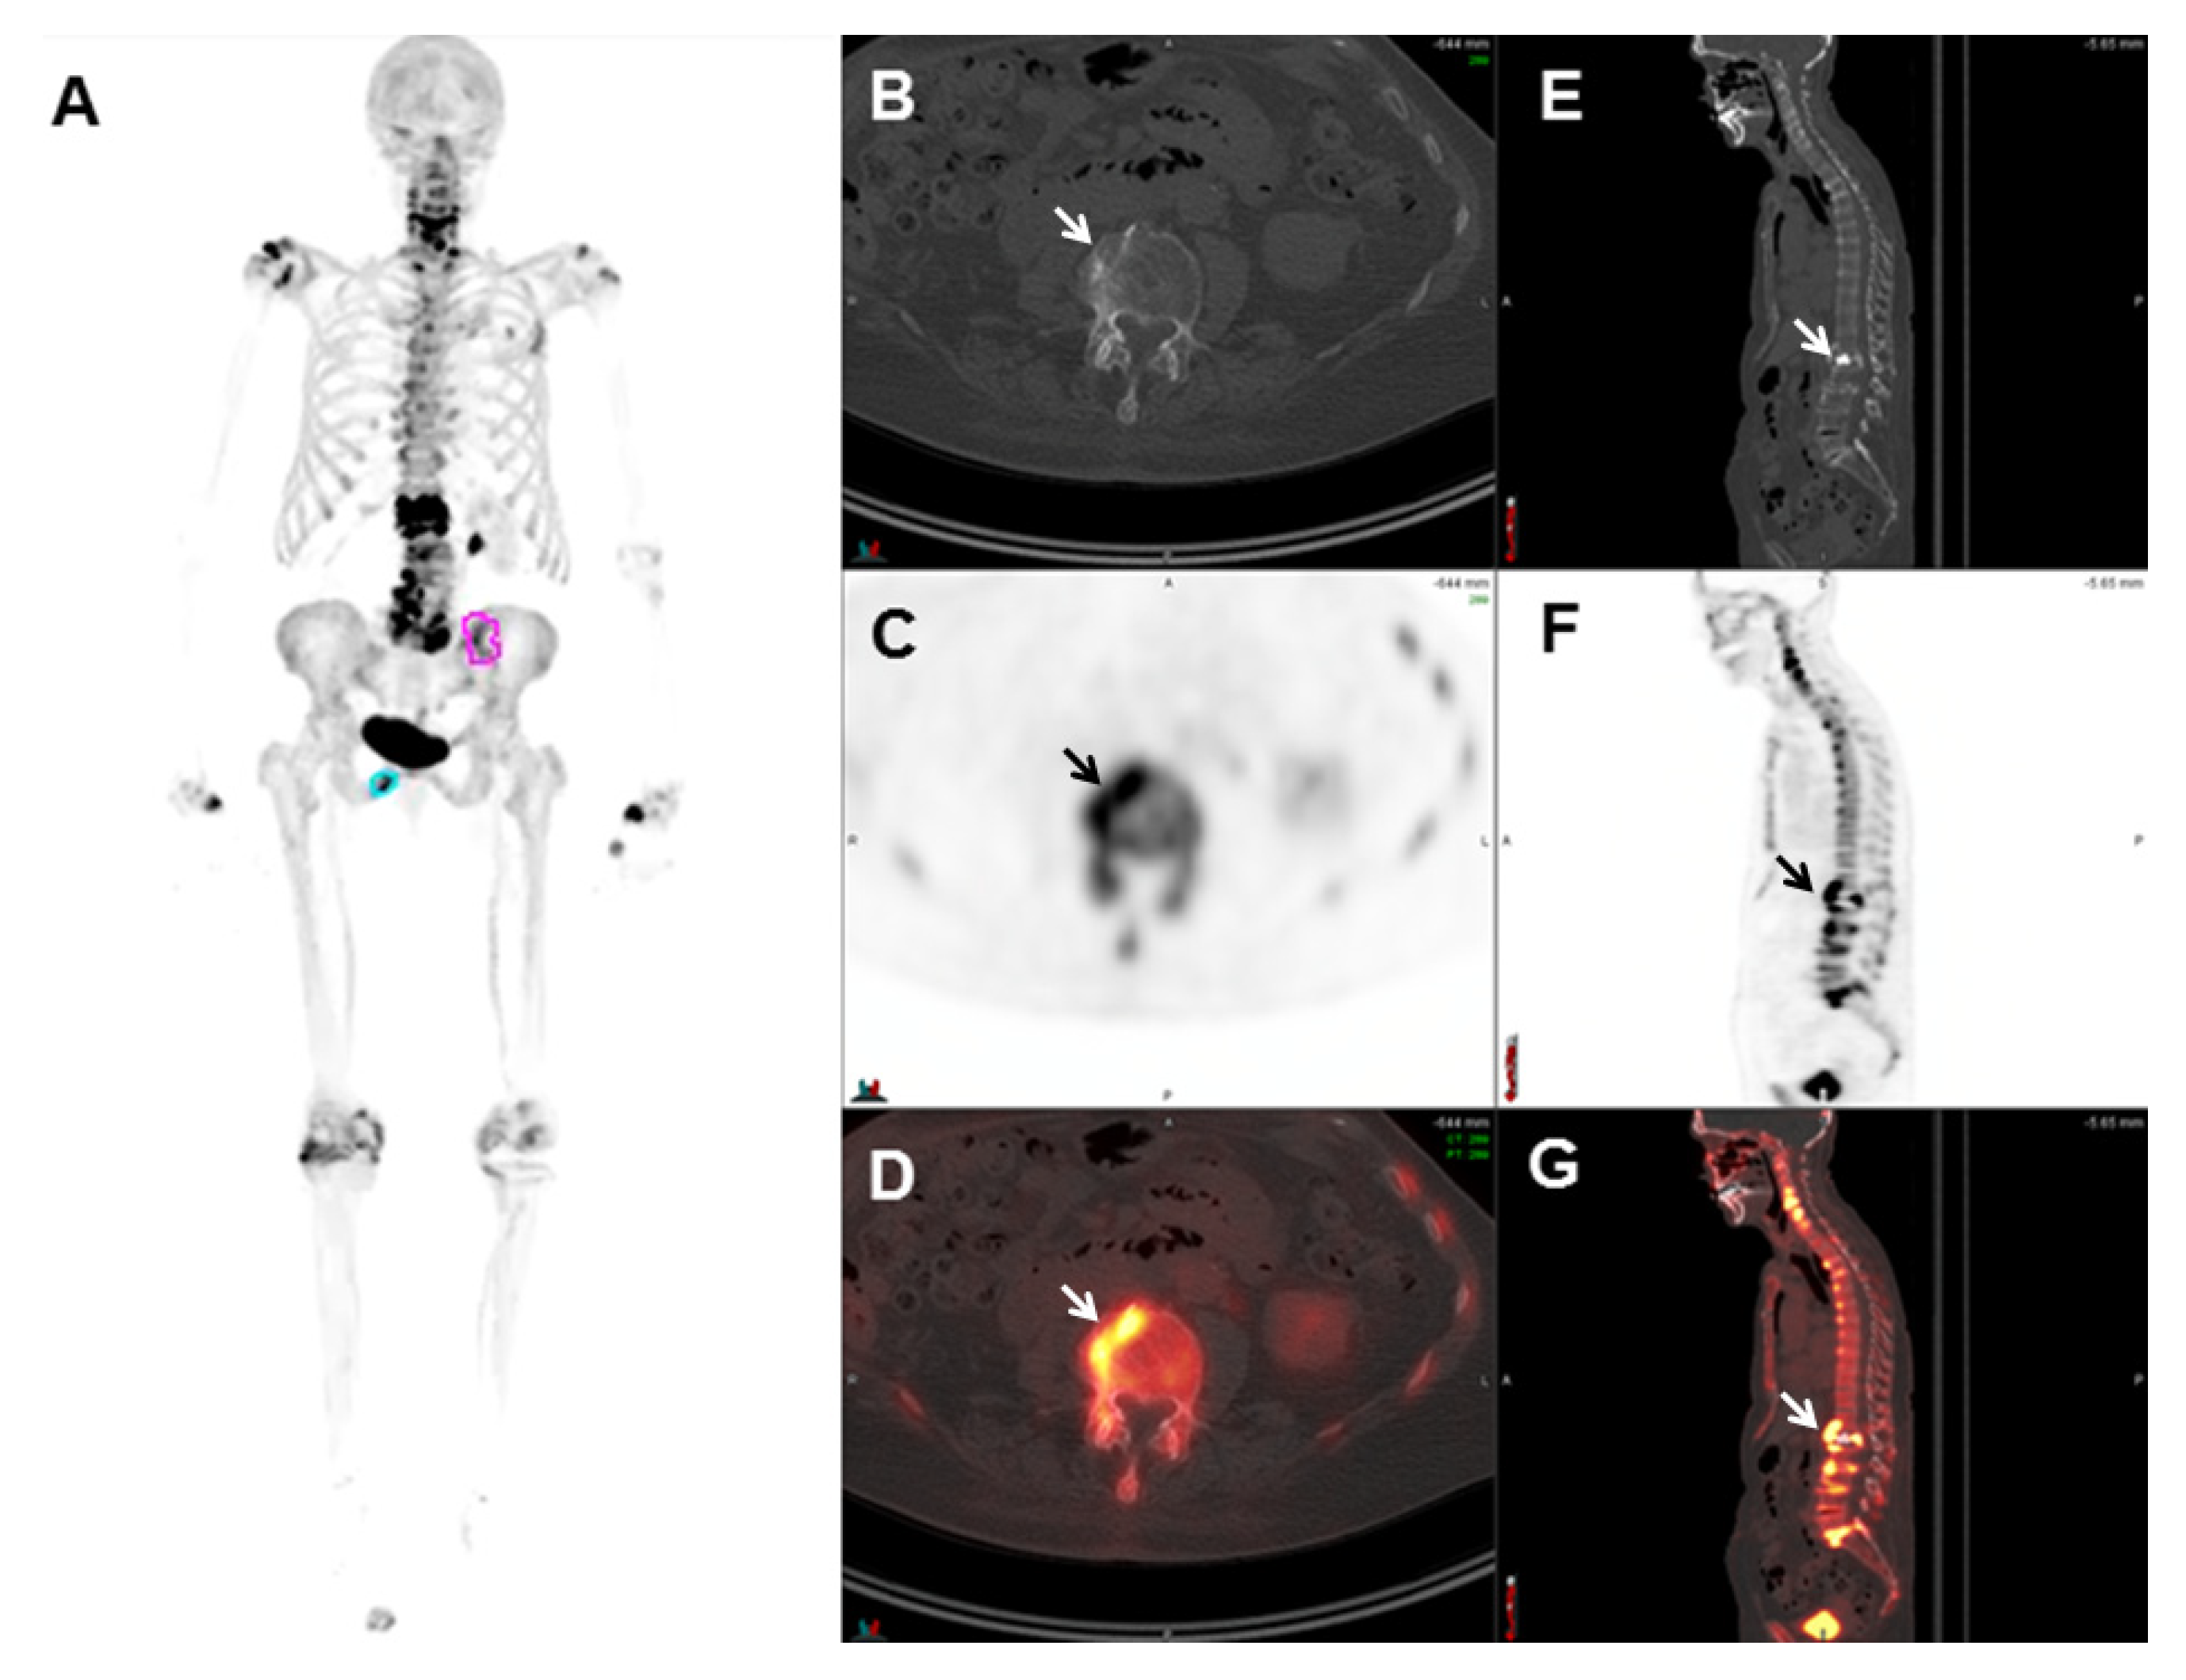

- Sachpekidis, C.; Eder, M.; Kopka, K.; Mier, W.; Hadaschik, B.A.; Haberkorn, U.; Dimitrakopoulou-Strauss, A. 68Ga-PSMA-11 dynamic PET/CT imaging in biochemical relapse of prostate cancer. Eur. J. Nucl. Med. Mol. Imaging 2016, 43, 1288–1299. [Google Scholar] [CrossRef]

- Rauscher, I.; Maurer, T.; Fendler, W.P.; Sommer, W.H.; Schwaiger, M.; Eiber, M. 68Ga-PSMA ligand PET/CT in patients with prostate cancer: How we review and report. Cancer Imaging 2016, 16, 14. [Google Scholar] [CrossRef]

- Hofman, M.S.; Hicks, R.J.; Maurer, T.; Eiber, M. Prostate-specific Membrane Antigen PET: Clinical Utility in Prostate Cancer, Normal Patterns, Pearls, and Pitfalls. Radiographics 2018, 38, 200–217. [Google Scholar] [CrossRef]

- Ceci, F.; Uprimny, C.; Nilica, B.; Geraldo, L.; Kendler, D.; Kroiss, A.; Bektic, J.; Horninger, W.; Lukas, P.; Decristoforo, C.; et al. 68Ga-PSMA PET/CT for restaging recurrent prostate cancer: Which factors are associated with PET/CT detection rate? Eur. J. Nucl. Med. Mol. Imaging 2015, 42, 1284–1294. [Google Scholar] [CrossRef]

- Perera, M.; Papa, N.; Christidis, D.; Wetherell, D.; Hofman, M.S.; Murphy, D.G.; Bolton, D.; Lawrentschuk, N. Sensitivity, Specificity, and Predictors of Positive 68Ga-Prostate-specific Membrane Antigen Positron Emission Tomography in Advanced Prostate Cancer: A Systematic Review and Meta-analysis. Eur. Urol. 2016, 70, 926–937. [Google Scholar] [CrossRef]

- Burgard, C.; Hoffmann, M.A.; Frei, M.; Buchholz, H.G.; Khreish, F.; Marlowe, R.J.; Schreckenberger, M.; Ezziddin, S.; Rosar, F. Detection Efficacy of 68Ga-PSMA-11 PET/CT in Biochemical Recurrence of Prostate Cancer with Very Low PSA Levels: A 7-Year, Two-Center “Real-World” Experience. Cancers 2023, 15, 1376. [Google Scholar] [CrossRef] [PubMed]